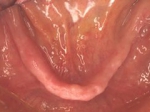

両側5歯症例

両側5歯症例両側5歯症例両側5歯症例 主訴-義歯のバネが壊れて手前の歯が痛んできた。 術前(旧義歯装着、鏡像) 術前(下顎粘膜面、鏡像)術前(下顎粘膜面、鏡像)術前(下顎粘膜面、鏡像) 術前レントゲン術前レントゲン術前レントゲン 術前口腔内(正面観)術前口腔内(正面観)術前口腔内(正面観)

術後(鏡像)術後(鏡像)術後(鏡像) 術後口腔内(正面観)術後口腔内(正面観)術後口腔内(正面観)もう入れ歯は要らなくなりました。 術後レントゲン術後レントゲン術後レントゲン